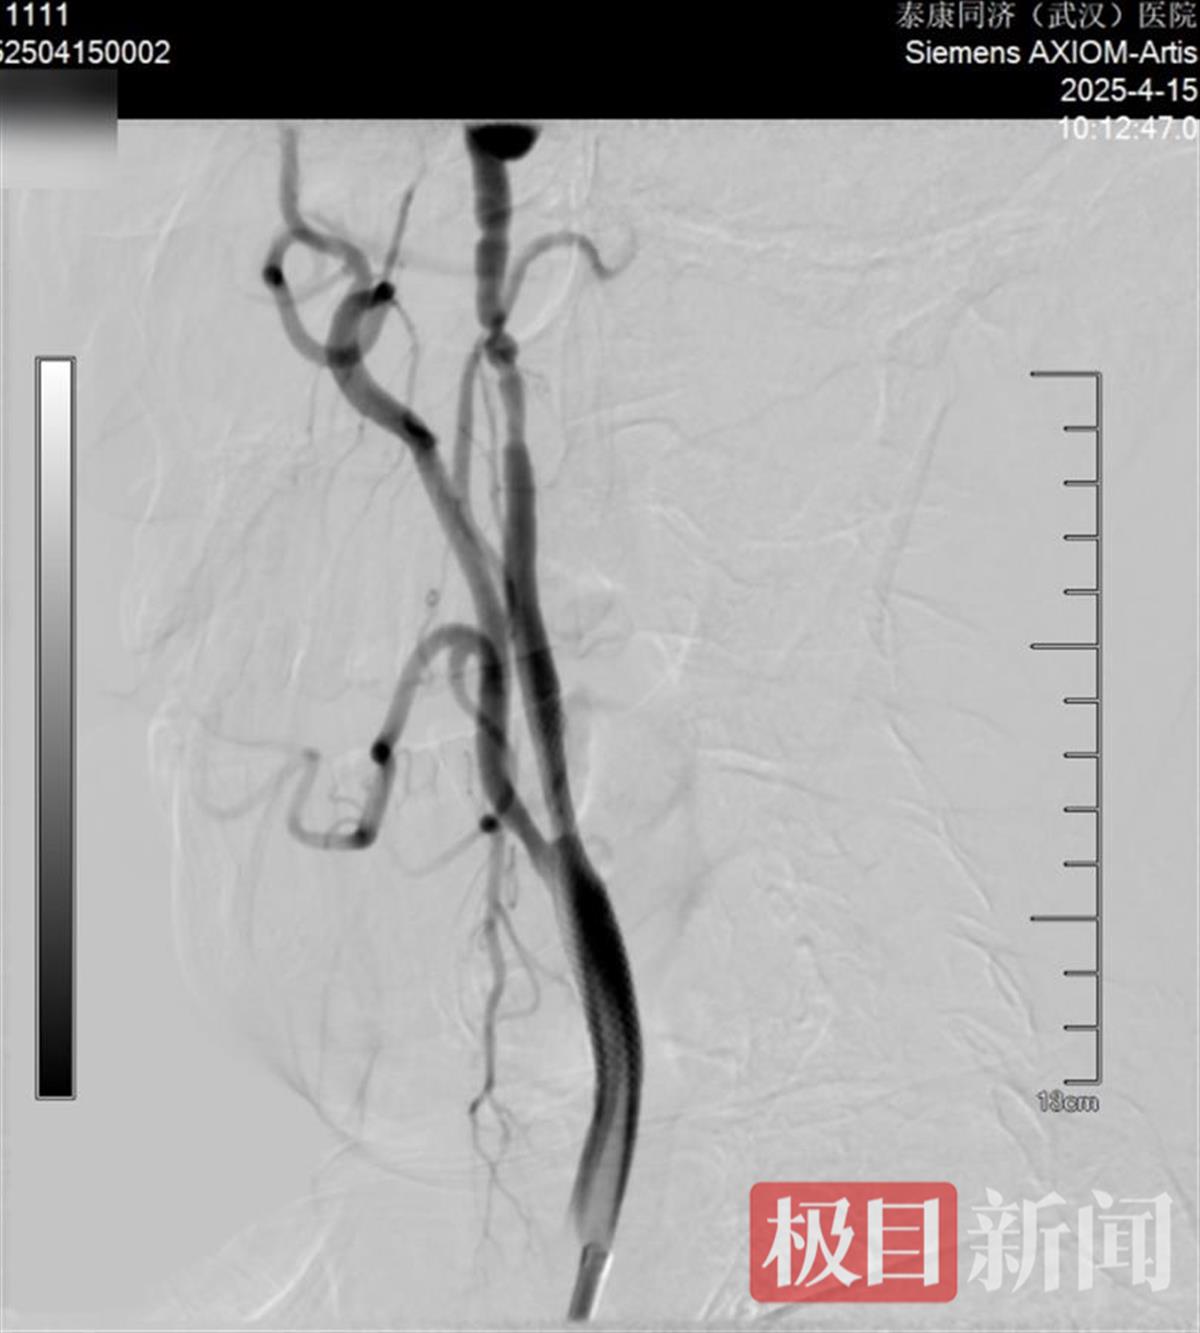

颈内动脉术前VS术后

近日,张庭保教授团队为患者实施“右侧颈内动脉球囊扩张术+支架植入术+左侧椎动脉药物球囊支架置入术”。术后脑血管造影显示,右侧颈内动脉及左椎动脉狭窄情况明显改善。患者术后恢复良好,目前已康复出院。